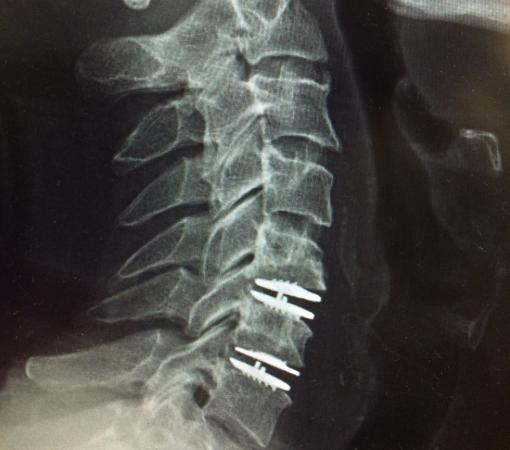

After consulting Synapse Spine, doctors diagnosed him with disc degeneration. They recommended disc replacement surgery in Mumbai as the best way to regain his active lifestyle. Just weeks after surgery, Arjun was pain-free and back to enjoying life.

At Synapse Spine, the worn-out disc is replaced with an artificial one, restoring spinal function. Disc replacement surgery in Mumbai helps patients regain mobility without the stiffness associated with spinal fusion.